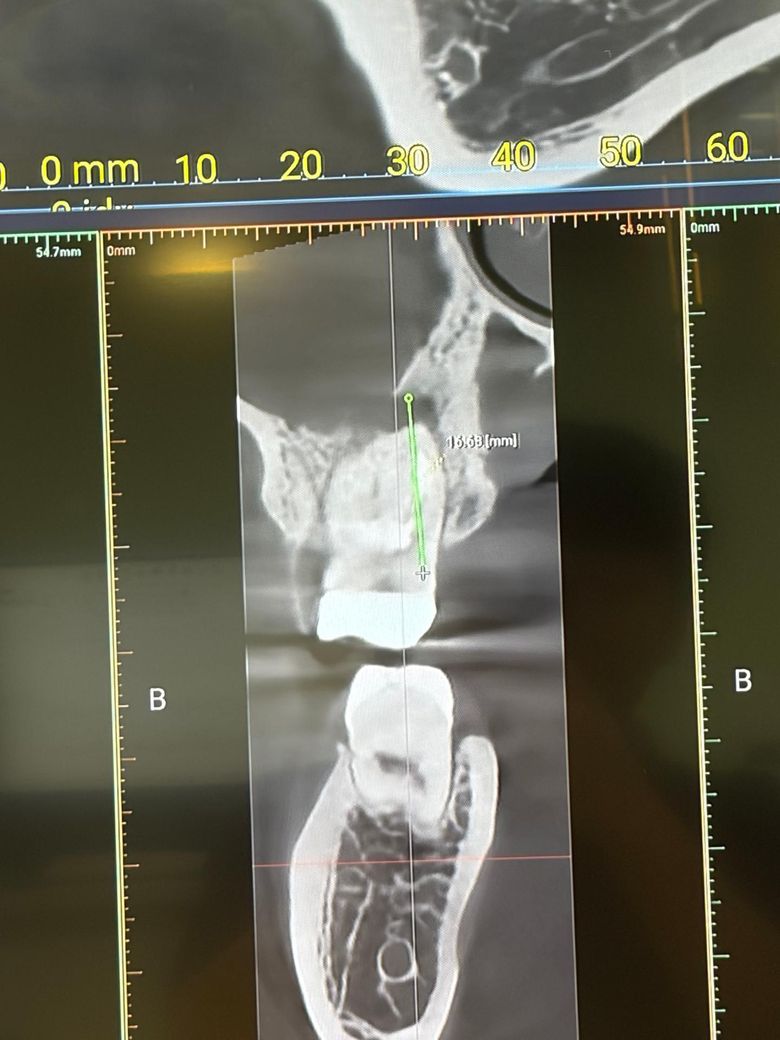

잇몸 뼈가 녹아서 임플란트를 해야한다고 합니다. 해당 치아는 신경치료 했었고, 크라운 씌운지 11년 되었습니다. 통증은 없는 상태인데 검진 받으러 가니까 이미 살릴 수 없고 뽑아야 한다고 하더라구요. 과잉진료는 아닐까요?

염증으로 주변 뼈는 녹고있는 상태입니다 앞으로 얼마나 빠르게 잇몸뼈가 흡수될지는 미지수이나 그대로 두면 계속 잇몸뼈가 녹을겁니다